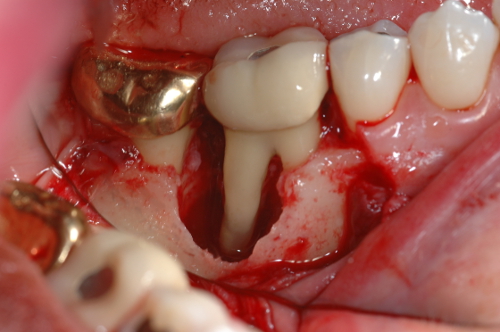

- A terapêutica periodontal regenerativa compreende os procedimentos executados com o objetivo de restaurarem os tecidos periodontais de suporte que foram perdidos, restabelecendo a arquitetura e a função. Pretende-se então, a regeneração do ligamento periodontal, novo cemento radicular e osso alveolar, melhorando a curto e longo-prazo o prognóstico de dentes periodontalmente comprometidos.

- Será feita a abordagem do conceito de Regeneração Tecidular Guiada (RTG): Aplicação clínica da RTG.

- Fatores associados ao paciente, ao tipo de defeito ósseo e à técnica cirúrgica.

- Serão discutidos vários casos clínicos da utilização da Regeneração Tecidular Guiada (RTG) e da utilização das proteínas derivadas da matriz de esmalte (Emdogain) na regeneração de defeitos infraósseos e/ou defeitos de furca.

Fotos dos casos clínicos